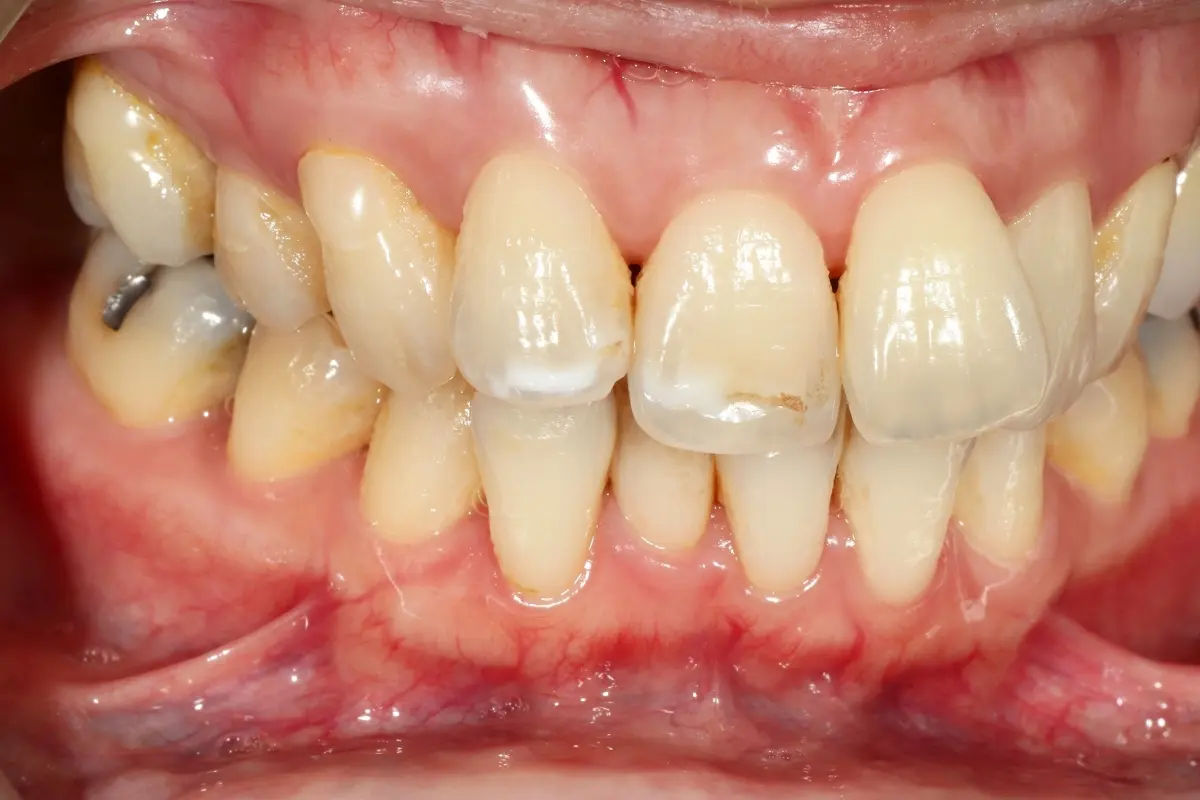

Dentist 陳昕 全口照護醫師 看診項目 前牙美學仿生樹脂補牙/全科牙醫 學經歷 臺北醫學大學牙醫系學士 前天主教新店耕莘醫院醫師 前臺北榮民總醫院醫師 亞洲齒列再生研究學會Advance植牙補綴專科訓練 微光私塾牙周雷射微創治療技術訓練 臺灣牙醫顯微美學治療學會會員醫師 中華審美牙醫學會會員醫師 CASE 案例分享 滲透型樹脂修復 主治醫師 陳昕 治療時間 單次療程 主訴 想處理前牙白白的色斑 前牙美學/仿生美學樹脂 主治醫師 陳昕 治療時間 單次療程 主訴 牙齒整齊,但門牙中間縫隙明顯,影響笑容美觀 前牙美學/陶瓷貼片 主治醫師 陳昕 治療時間 約1個月 主訴 兩顆門牙缺角,想要重建外觀 前牙美學/滲透型樹脂修復 主治醫師 陳昕 治療時間 單次療程 主訴 門牙有長期存在的白斑與表面不平整,影響外觀與自信 前牙美學/仿生美學樹脂 主治醫師 陳昕 治療時間 約兩週 主訴 矯正後的黑三角縫問題 前牙美學/仿生美學樹脂 主治醫師 陳昕 治療時間 約三週 主訴 因牙周病產生的黑三角縫 前牙美學/牙冠增長術、仿生全瓷牙冠 主治醫師 陳昕 治療時間 約6個月 主訴 牙齒排列不整、假牙外觀不自然 前牙美學/仿生美學樹脂 主治醫師 陳昕 治療時間 約兩週 主訴 露齒笑時黑三角縫明顯,覺得不好看 前牙美學/仿生美學樹脂+噴砂美白 主治醫師 陳昕 治療時間 約兩週 主訴 露齒笑時有不好看的黑三角縫,容易有茶垢沉澱,讓縫隙更明顯 牙齒美白/噴砂美白+冷光美白 主治醫師 陳昕 治療時間 單次療程 主訴 前牙泛黃且染色明顯,影響外觀與自信 牙齒美白/噴砂美白 主治醫師 陳昕 治療時間 單次療程 主訴 牙齒表面有喝咖啡、抽菸造成的外部染色,影響外觀與自信 點此載入更多 Column 精選文章 FEATURED 精選案例 【牙科修復案例】陶瓷貼片可以做一顆嗎?單顆門牙缺角修復,陶瓷貼片重建自然笑容 2026-01-16 從「假笑」到「自然笑容」的轉變——認識「牙冠增長術」與「仿生全瓷冠」 2025-10-14 Video 精選影音